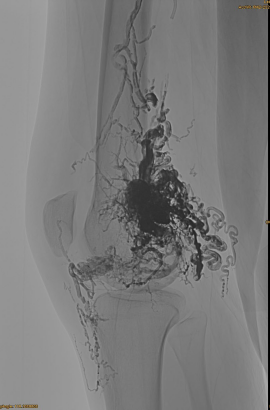

DSA ban đầu:

Kết quả cuối cùng:

Hầu như không có bất kỳ dòng chảy tĩnh mạch nào:

Giai đoạn muộn, một EMBO khác cần thiết, nhưng tốt hơn nhiều: